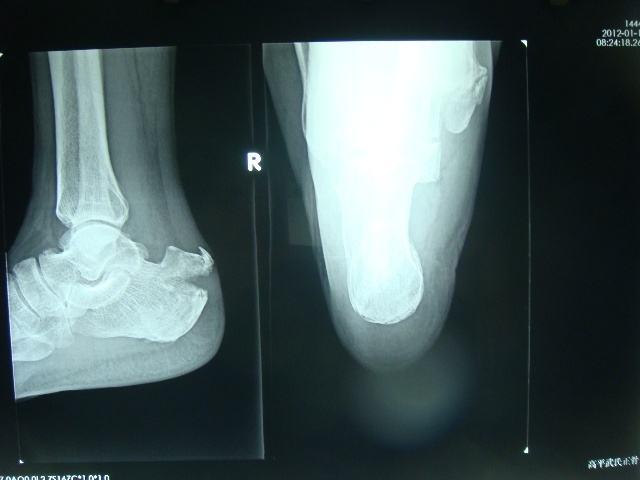

跟骨骨折在临床足部骨折中比较常见,多发生于成年人。大部分是由于高空坠落时足跟着地造成垂直撞击所致,车祸、运动伤害、挤压伤等也可造成跟骨骨折,骨折后多情况复杂,主要特征是距下关节的压缩和关节面下方的骨结构碎裂,在高空跌落中若冲击力足够大,有时会伴有脊椎和骨盆的损伤。跟骨骨折轻者为轻微移位骨折,严重的导致粉碎性骨折。临床上表现为足跟疼痛不能站立或行走,甚至肿胀压痛,有的出现功能障碍、局部畸形和骨擦音,足踝部活动受限,还可见瘀血斑。

跟骨高度,宽度,关节面不正常,或者骨折片移位太明显,那么需要手术,手术后的的除了伤口需要换药,不用打石膏,可以马上进行锻炼,同时定时冰敷,可以防止减轻疼痛,防止僵硬,促进消肿,其他类似。抬高患肢和活动足趾,然后逐渐活动膝关节,然后活动踝关节,我认为是最重要的。也可以应用一些消肿的药物,快速消肿极为重要!